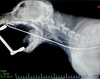

For the past 8 years, Veterinary Practice News has had an annual x-ray contest for the craziest things pet's have eaten. Here are the winners for 2013.